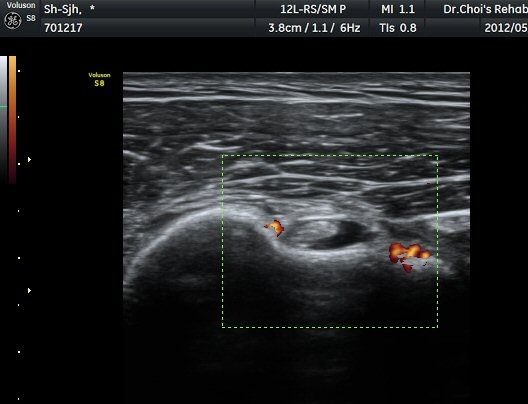

µÈ´Ù(»çÁø 3). ±Ø»ó°Ç Á¾´Ü¸é°Ë»ç»ó ±Ø»ó°Ç ºÎÂøºÎ¿¡ °í¿¡ÄÚ µ¢¾î¸®°¡ °üÂûµÇ°í(»çÁø 4, 5)

ÆÄ¿öµµÇ÷¯ °Ë»ç¿¡¼­ Ç÷·ùÁõ°¡¸¦ º¸ÀδÙ(»çÁø 6).  Ⱦ´Ü¸é°Ë»ç¿¡¼­µµ °í¿¡ÄÚ µ¢¾î¸®¿Í

Ç÷·ùÁõ°¡°¡ È®ÀεȴÙ(»çÁø 7, 8).